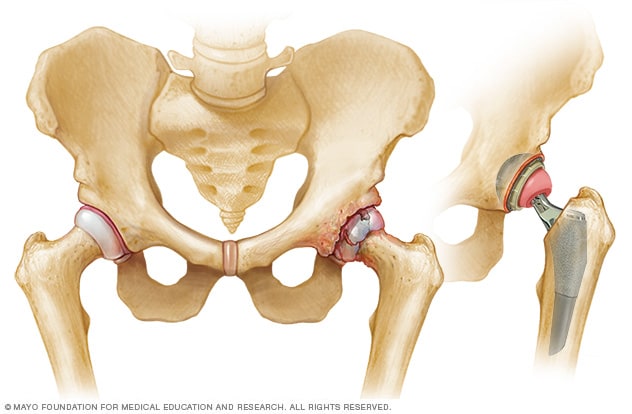

Artificial hip

Artificial hip

Hip prostheses are designed to mimic the ball-and-socket action of the hip joint. During hip replacement, a surgeon removes the diseased or damaged parts of the hip joint and inserts the artificial joint.

Hip replacement is surgery to remove damaged sections of the hip joint and replace them. Replacement parts are usually made of metal, ceramic and hard plastic. This artificial joint, called a prosthesis, helps reduce pain and improve function.